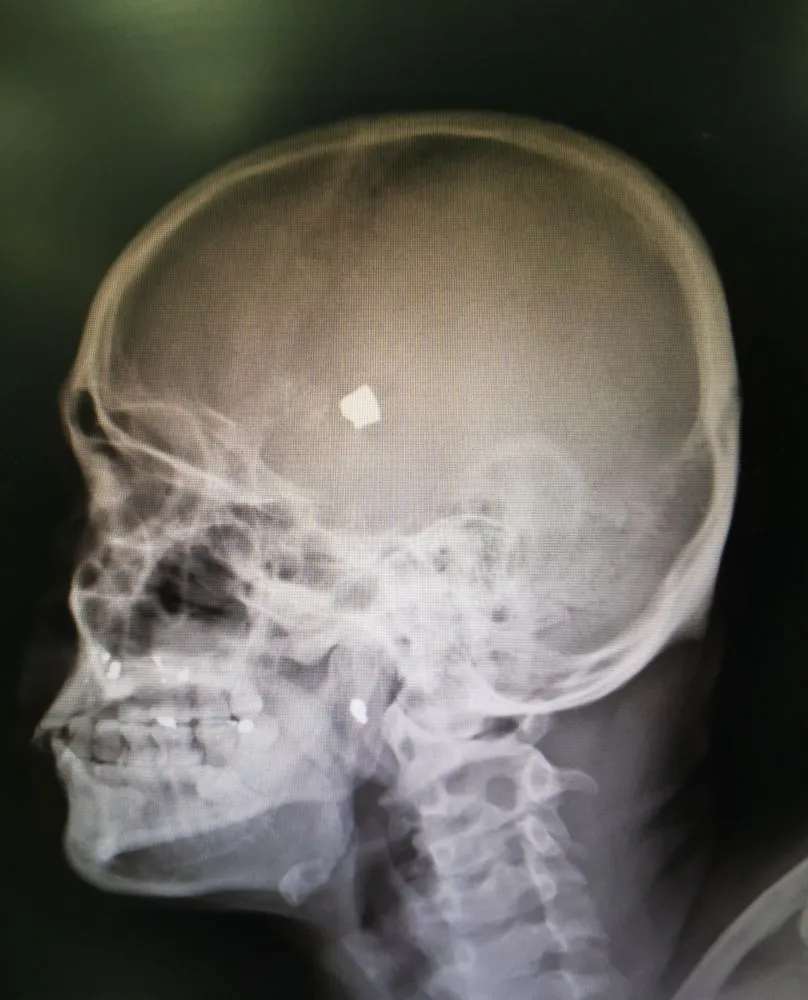

The chance of surviving a headshot has its roots in the physics of the bullet and the biology of our bodies. Thus, a person’s odds of surviving a headshot trauma depend on the type and size of the bullet, its velocity, its trajectory, and the entry and exit point of the bullet. So, to begin, let’s try to understand the science of headshots and the aftermath of getting hit by a bullet.

The most important factor from a biological standpoint to determine survivability from a gunshot is the location where the bullet hits and passes through. The brain is a marvelous mystery, with each little cluster governing specific vital and not-so-vital functions of the body. Responsible for controlling involuntary actions, for example, the brain stem is a critical part of our body. A shot directed towards it is often fatal. The degree of injury would depend on which region the bullet penetrates through.

There is also a much greater chance of surviving a front-to-back gunshot than a gunshot received from the side. This is because, in the case of a front-to-back gunshot, it’s possible that the bullet will only damage one hemisphere of the brain, while the other is left unaffected. Our brain is a resilient organ, comparable to a twin-engine plane that can work even upon losing one engine. Major functions like cognition and speech are shared between the two hemispheres of the brain, so if one hemisphere is left intact by the bullet, the individual still has a decent chance of bouncing back from the ordeal, though never again with complete psychological and physical health.

However, the case of the skull is unique, on account of its enclosed structure. If a high-speed bullet is fired into the skull, the skull bears the full brunt of the force, leading to skull fractures. Skull shards that pierce the brain at that point are even more difficult to remove than the bullet itself. If the skull is subjected to a high-speed, but small bullet, the worry is that the tiny bullet would ricochet around after entering the brain cavity, damaging several areas of the brain at once. The best-case scenario for survival is therefore a small, low-velocity bullet fired from a distance… with a low-caliber gun.